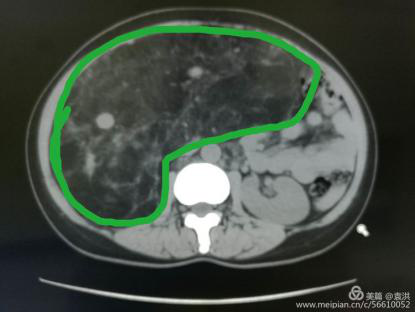

這一檢查讓婦科醫(yī)生也大吃一驚!醫(yī)生檢查時(shí)觸及腹部一硬質(zhì)包塊,無(wú)明顯邊界,上至劍突下,下至盆腔,兩側(cè)至腋中線,無(wú)壓痛,固定,說(shuō)明這包塊占據(jù)了患者整個(gè)腹腔,考慮來(lái)源于其它臟器,立即行全腹CT檢查??苫颊哂忻荛]空間綜合癥,一開(kāi)始拒絕CT檢查,醫(yī)生反復(fù)給患者做思想工作,并強(qiáng)調(diào)此項(xiàng)檢查的重要性,患者足足猶豫了兩天,才終于在醫(yī)護(hù)人員及家屬的鼓勵(lì)下順利完成了檢查。腹部CT提示,高度懷疑右腎有一顆脂肪肉瘤。

遂請(qǐng)泌尿外科會(huì)診協(xié)助診治,經(jīng)檢查,結(jié)合CT考慮腎周?chē)蚋鼓ず竽[瘤。最終診斷為:右腎巨大脂肪肉瘤。且腫瘤從腹腔延至盆腔,腹腔臟器受壓推移。醫(yī)生建議,子宮肌瘤多為良性,不影響生命,可暫緩手術(shù),但右腎巨大脂肪肉瘤必須盡快手術(shù)摘除。